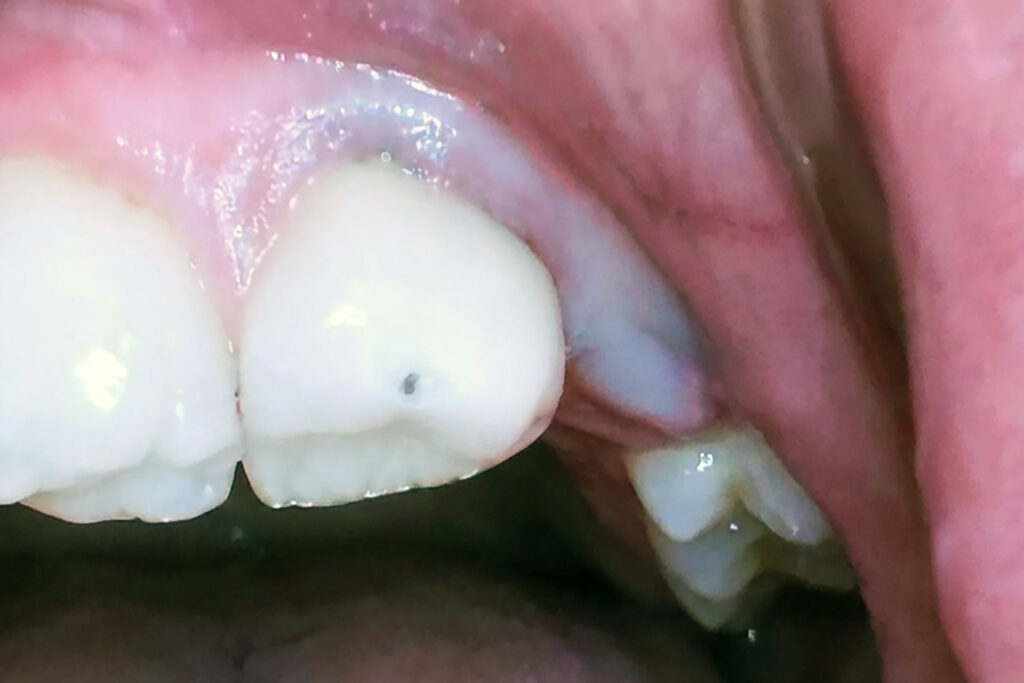

When this happens, a small pocket of gum tissue called an operculum may form over the tooth when wisdom teeth partially erupt. This pocket collects food particles and bacteria, creating the perfect environment for infection and inflammation. Excess gum tissue can trap bacteria and debris, increasing the risk of infection.

The result is a swollen gum over a wisdom tooth, often tender to the touch and sometimes with pus or bad breath. If left untreated, a swollen wisdom tooth can progress from mild irritation to an acute infection that affects both the soft tissue and the bone around the tooth. Untreated pericoronitis, the medical term for an inflamed gum near an erupting tooth, can lead to abscess formation, a painful pocket of pus that may require minor oral surgery or more invasive treatment.